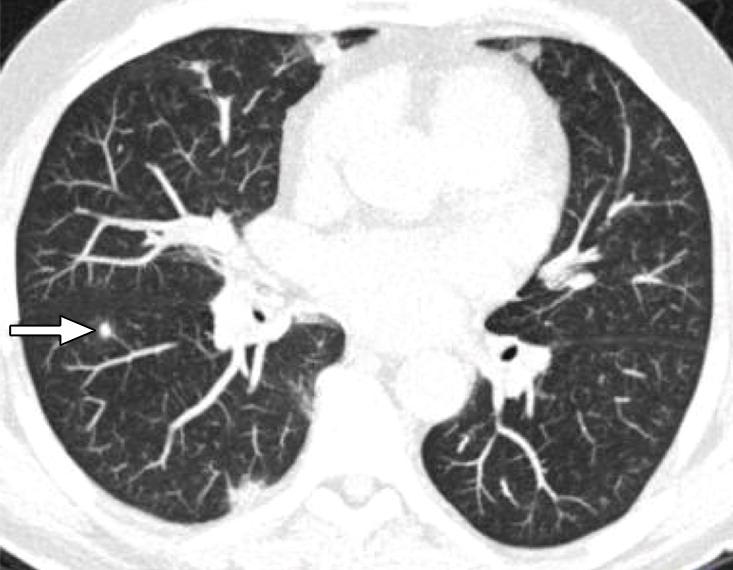

Resolving pulmonary nodules share CT features with malignant nodules.